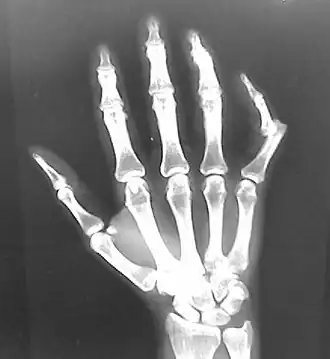

- Wrist

- Finger

- Interphalangeal (IP) or metacarpophalangeal (MCP) joint dislocations[41]

- In the United States, men are most likely to sustain a finger dislocation with an incidence rate of 17.8 per 100,000 person-years.[42] Women have an incidence rate of 4.65 per 100,000 person-years.[42] The average age group that sustain a finger dislocation are between 15 and 19 years old.[42]

- The most common dislocations are in the proximal interphalangeal (PIP) joints.[8]